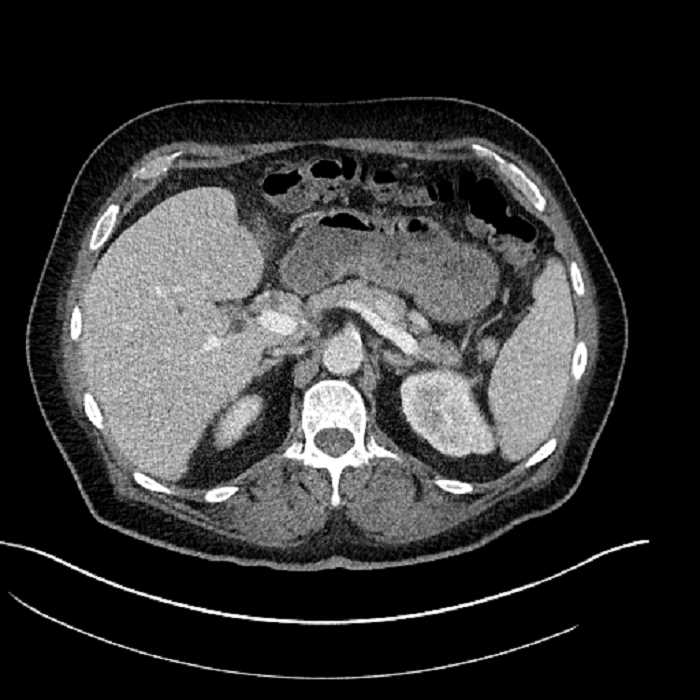

Age: 63

Sex: Male

Indication: Abdominal pain

• Large fluid density structure in hepatic segments 7 and 8 measuring 10 x 7 x 7 cm with internal septation and circumferential ill-defined low density compatible with edema

• Peripherally enhancing subcapsular collections along the anterior margin of the left hepatic lobe measuring 3 x 1 cm and 2 x 1 cm

• Clearly marginated fluid density structure in segment 7 and several other scattered tiny hypodensities, which likely represent cysts

• Hepatic abscess

Acute sigmoid diverticulitis complicated by a small contained perforation and a large abscess in the right hepatic lobe. Additional small subcapsular abscesses along the anterior margin of the left hepatic lobe.

• The classic CT imaging appearance is a double target sign with internal low density surrounded by an internal enhancing rim (capsule) and a low density external rim (edema)

Hepatic abscess showing the double target sign with low density internally surrounded by a thin inner enhancing rim (red arrow) and ill-defined outer low density rim (yellow arrow). Blue arrow indicates an internal septation. Red arrows: additional smaller subcapsular abscesses. Red arrow: focal contained perforation associated with diverticulitis.